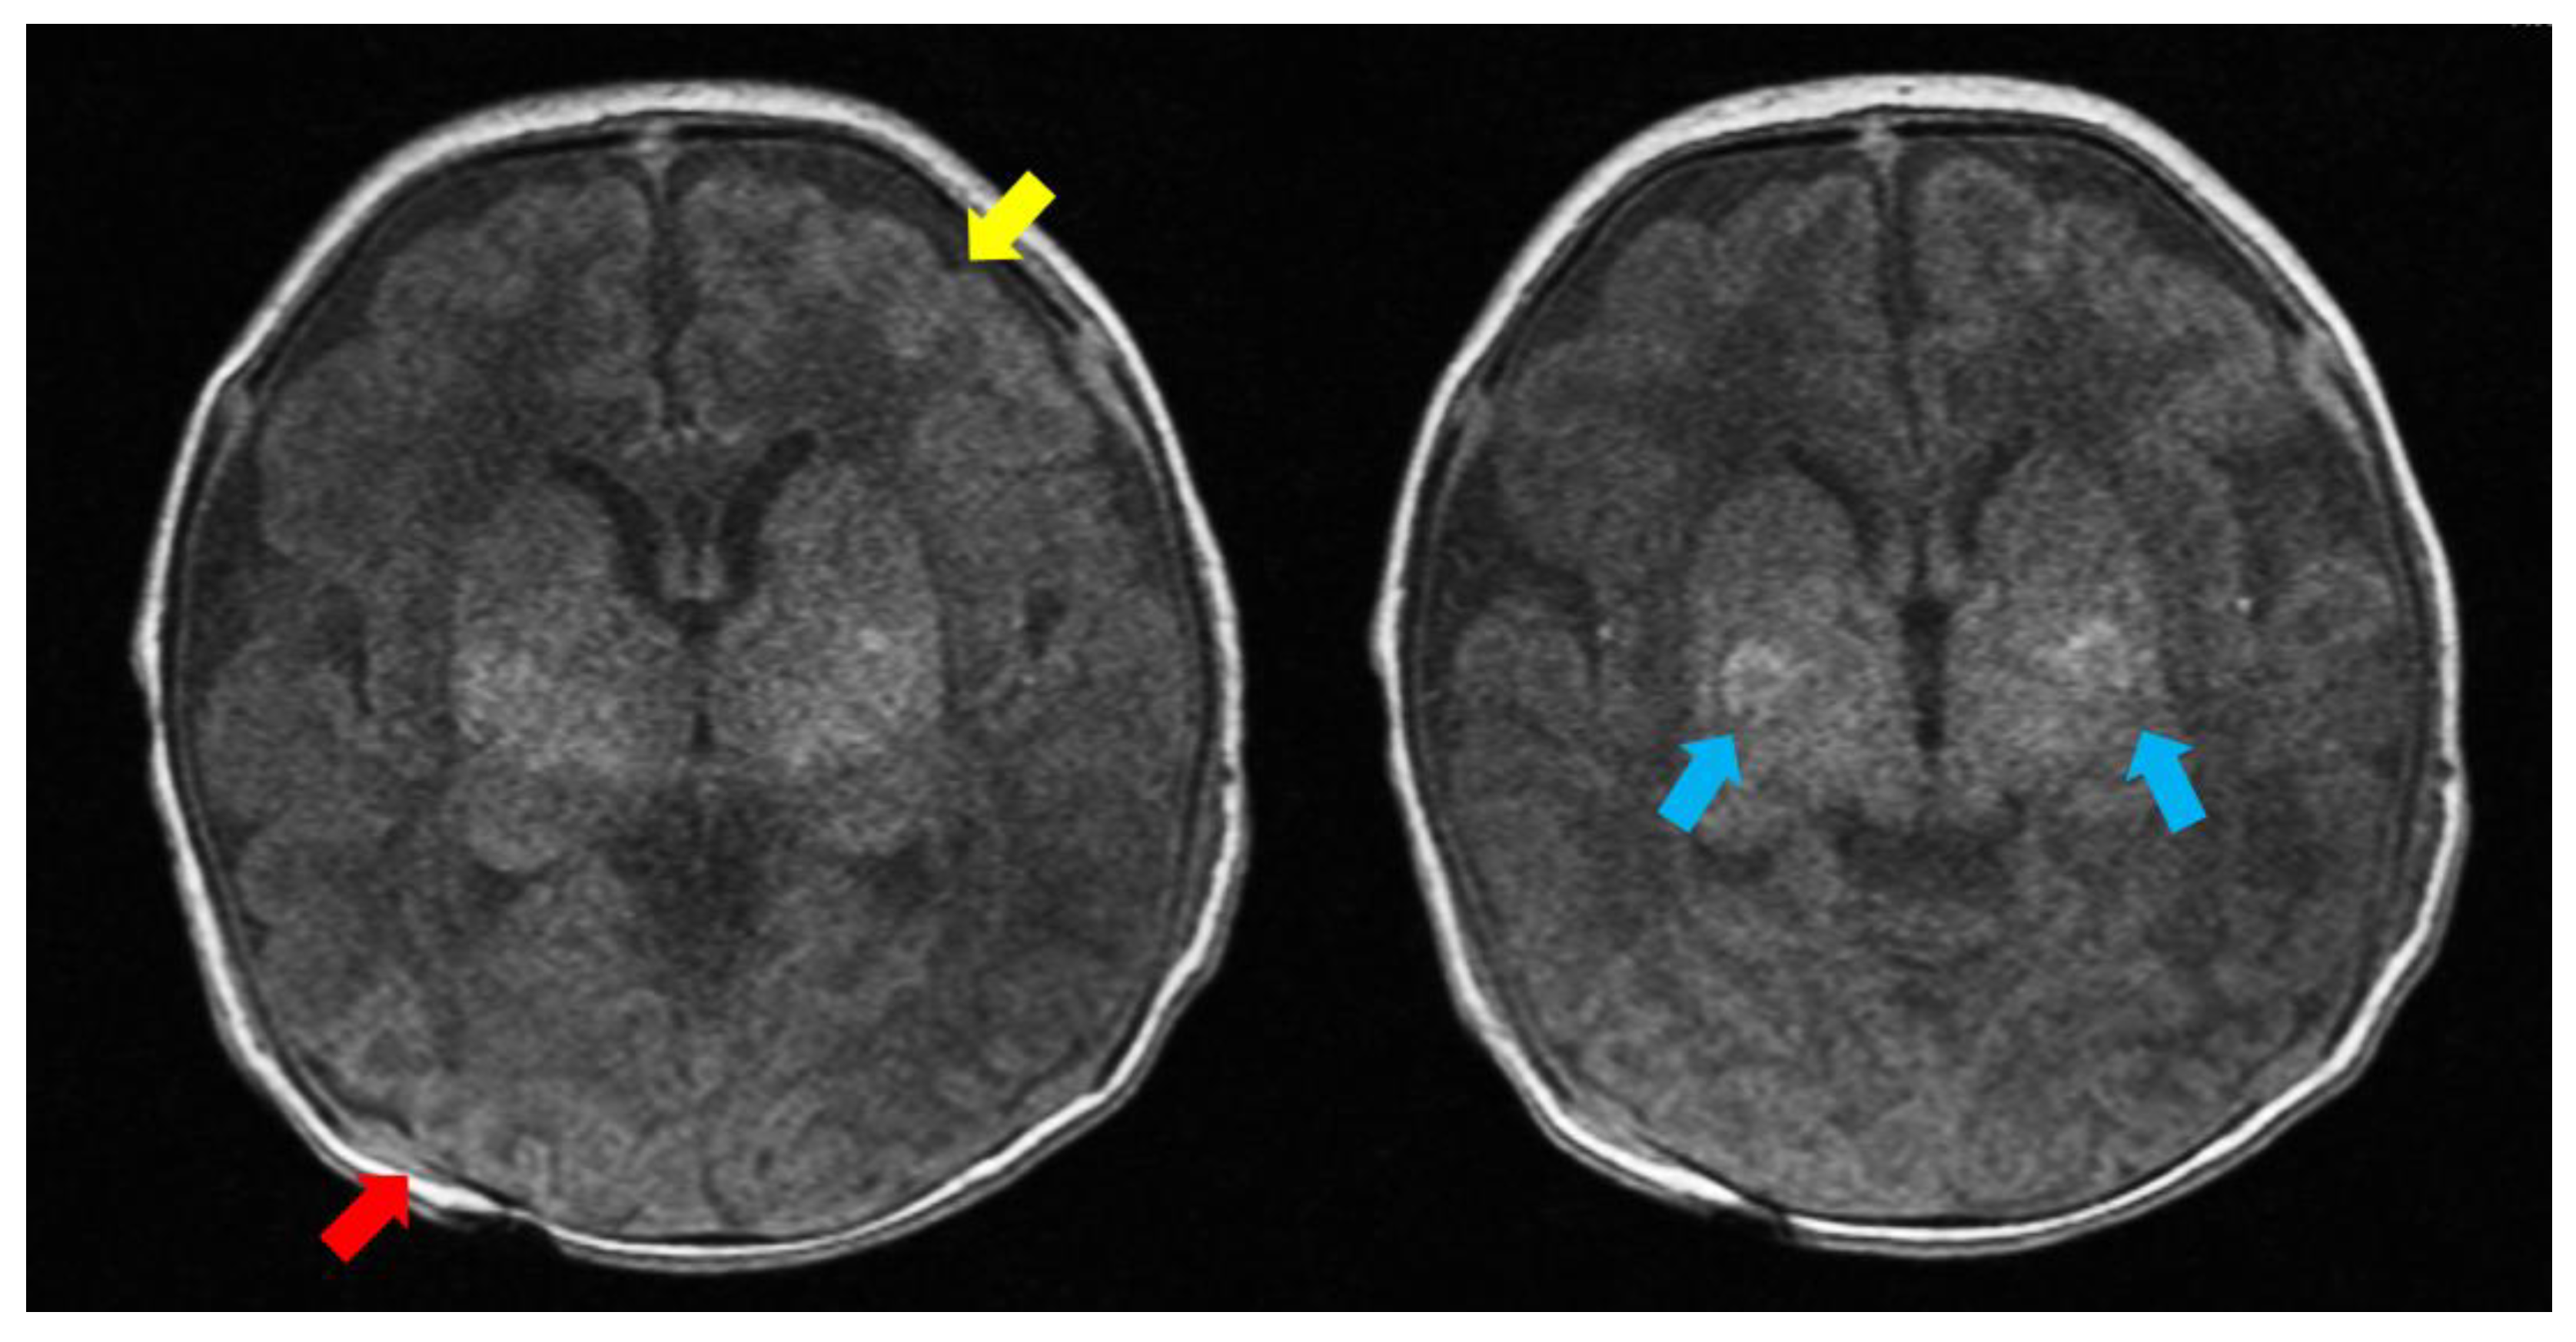

2. Case Description